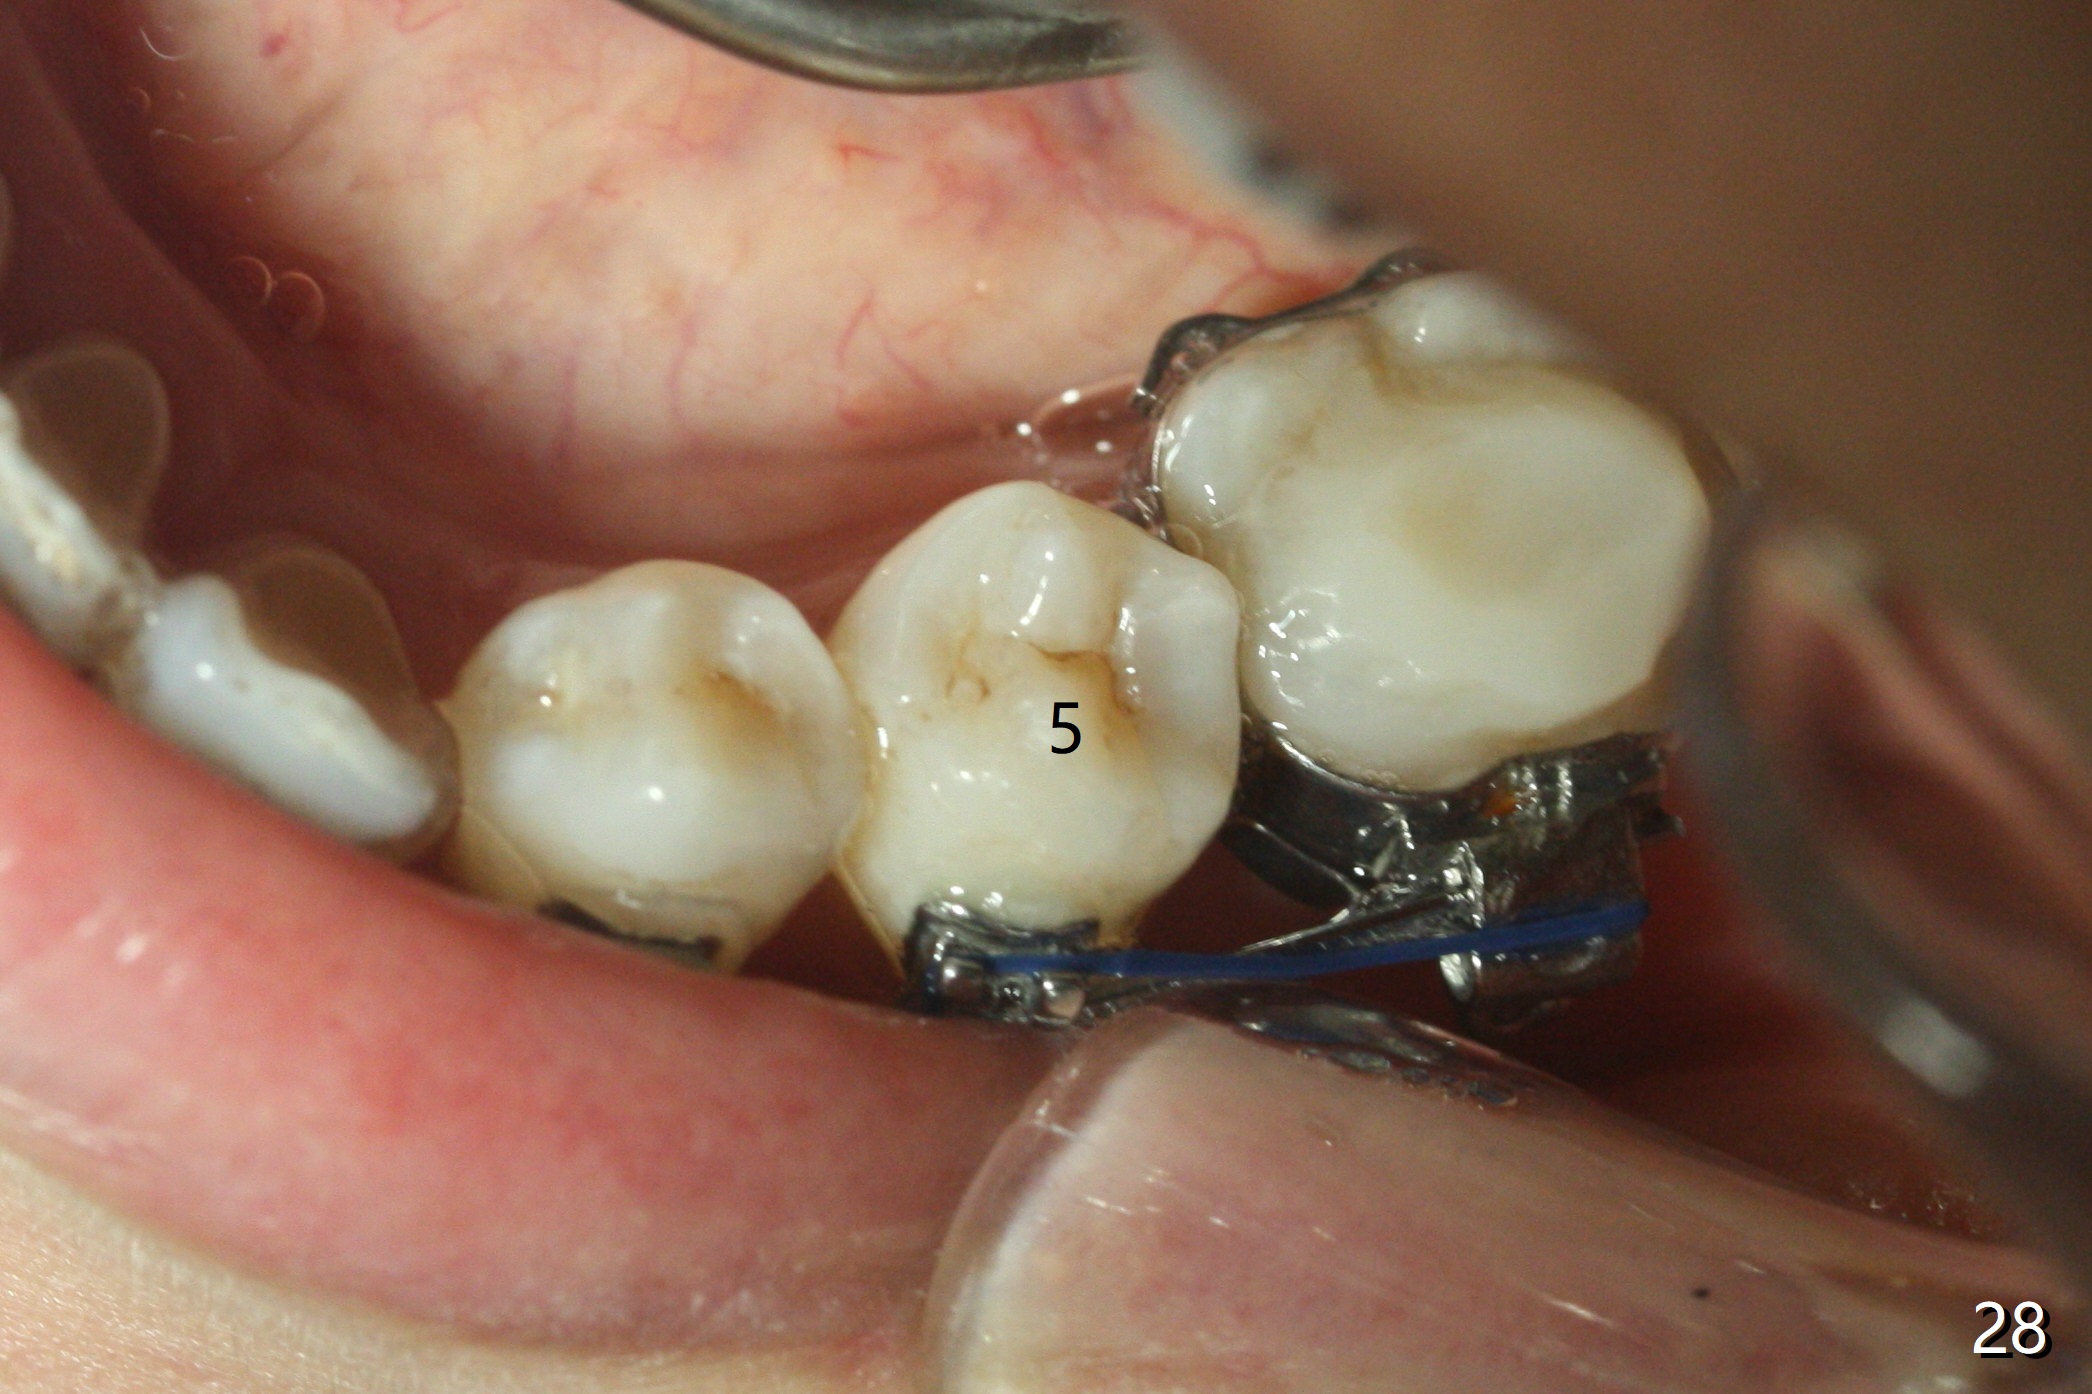

Eight months post banding, UR3 appears to be distalized with de-rotation (Fig.26), while UL3 is slightly over-distalized with mesial space (Fig.27 arrow). LL5 remains rotated (Fig.28). One months later, anterior over bite and over jet seem to be normal. In spite of lack of Class I anterior occlusion, it is decided that the upper posterior teeth should be mesialized. Next visit, wires will be changed to 16x16 with ligature wire between U3-3 and power chains between U3 and 5.